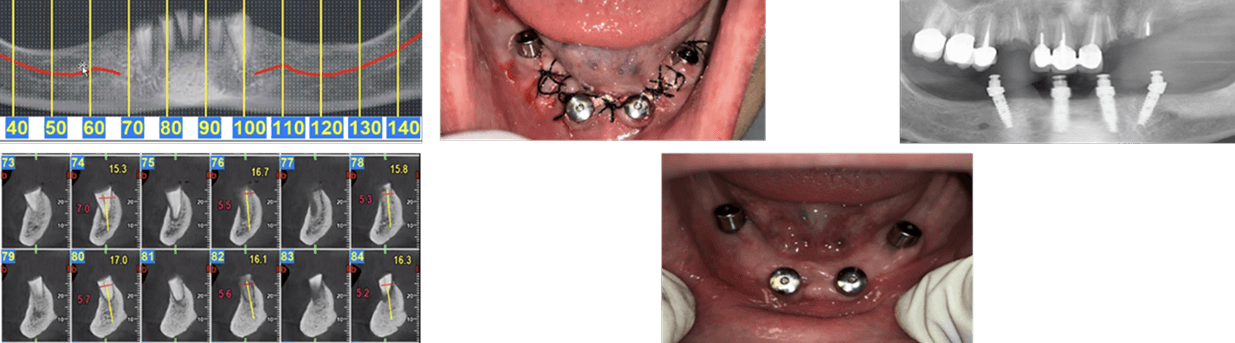

This case, performed by Prof. Alberto Monje, involved a patient diagnosed with inflammatory environment, presenting with advanced bone loss and bleeding on probing. The treatment followed a surgical regenerative protocol combining mechanical decontamination and biological stimulation using the MAGDENT Miniaturized Electromagnetic Device (MED). The procedure included implantoplasty, thorough surface debridement and decontamination, and guided bone regeneration (GBR) with a particulate bone graft and collagen membrane to restore the lost peri-implant bone structure. Immediately after the regenerative procedure, the MED healing abutment was connected to the implant and left in place for three weeks, delivering continuous pulsed electromagnetic field (PEMF) stimulation to promote cellular activation, angiogenesis, and bone remodeling at the defect site.

After soft tissue stabilization, the prosthesis was reinstalled, and long-term follow-up at 11 months demonstrated excellent clinical and radiographic outcomes. The treated site exhibited complete mucosal healing, absence of inflammation or pocketing, and stable bone regeneration with clear re-establishment of crestal bone levels around the implant. Radiographs confirmed maintenance of the regenerated bone volume and implant stability, while clinical evaluation showed healthy peri-implant tissues with ideal color, tone, and contour.

• This case highlights the effectiveness of the surgical inflammatory environment management protocol integrating PEMF technology, showing how the MED device can enhance bone regeneration and accelerate healing when combined with conventional regenerative techniques such as implantoplasty and GBR. The synergy between surgical decontamination and electromagnetic stimulation supports a predictable, biologically driven regeneration in peri-implant defects, offering a viable alternative to more invasive resection procedures.

Inflammatory environment Surgical Regeneration (Prof. Alberto Monje, DDS, MS, PhD) This clinical case, documented by Prof. Alberto Monje and published in Periodontology 2000 (“Emerging locally delivered antimicrobial and immunomodulatory approaches for the prevention/treatment of peri-implant diseases,” Monje et al., DOI: 10.1111/prd.12638), presents a surgically managed inflammatory environment defect with the integration of Magdent’s Miniaturized Electromagnetic Device (MED) as an adjunctive regenerative tool. The patient was diagnosed with inflammatory environment accompanied by inflammation and progressive bone loss (A–B). The disease had persisted despite prior nonsurgical therapy (C). During the surgical phase, granulation tissue was meticulously removed by curettage (D), and implantoplasty was performed on the exposed implant surface to smooth irregularities and reduce bacterial adhesion (E). Subsequent electrolytic decontamination of the intrabony area was performed using the GalvoSurge system (F), ensuring optimal surface disinfection prior to regeneration. Following decontamination, a guided bone regeneration (GBR) procedure was performed using a particulate bone graft, after which the Magdent PEMF healing abutment was immediately connected to the implant (G). The MED device delivered pulsed electromagnetic field (PEMF) stimulation over a period of three weeks, enhancing cellular activity, vascularization, and bone remodeling during the early healing phase.

At 9 months, clinical evaluation revealed complete soft tissue healing, resolution of inflammation, and reestablishment of mucosal seal (H). At 1-year follow-up, radiographs confirmed substantial bone regeneration and defect fill with stable crestal bone levels and restored implant function (I).

• This case underscores the clinical efficacy of combining regenerative surgery, decontamination, and electromagnetic stimulation. The synergy between implantoplasty, electrolytic cleaning, and Magdent PEMF therapy demonstrates a predictable, minimally invasive, and biologically enhanced approach to inflammatory environment management, providing both functional and histological regeneration outcomes in previously compromised implant sites.